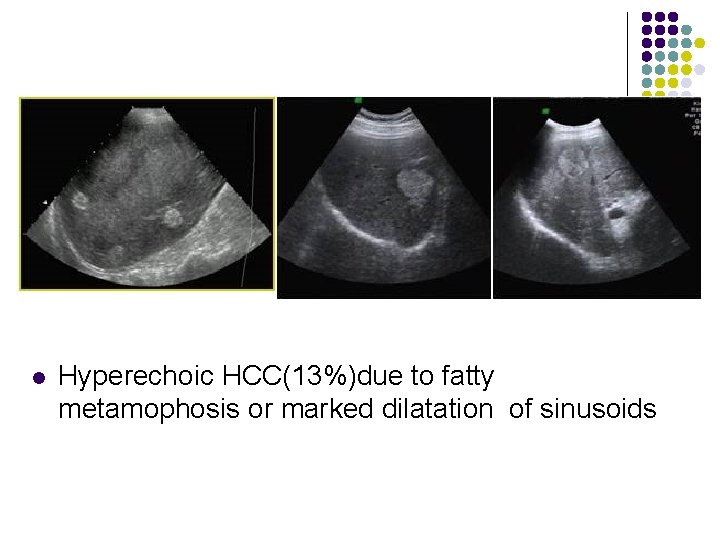

Sonographic Features of HCC l l l 86 -99% sensitivity; 90 -93% specificity; 65 -94% accuracy; Hyperechoic HCC(13%)due to fatty metamophosis or marked dilatation of sinusoids Hypoechoic HCC(26%)due to solid tumor HCC of mixed echogenicity (61%)due to nonliquefactive tumor necrosis

l Hyperechoic HCC(13%)due to fatty metamophosis or marked dilatation of sinusoids